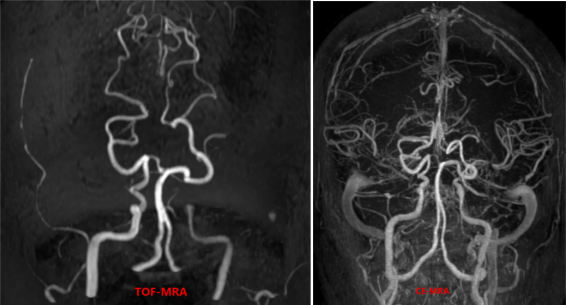

2招丨鉴别烟雾病起因

4a3f949703afaff49bceeb50c8e42009.png6f8e0e6e18d899bde5dea1f66560ec8b.png

以上4图发现右侧颈内动脉和左侧颈内动脉末端,大脑中动脉M1M2段多发斑块形成并严重狭窄,颅内多发小血管生成,大脑后动脉代偿性增粗,并部分大脑前动脉交通,考虑为血管内斑块引起的烟雾综合征。